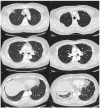

In this study, we aimed to assess the prevalence of interstitial lung abnormalities (ILAs) and investigate the rates and risk factors associated with radiologic ILA progression among patients with lung cancer following surgical resection. Patients who underwent surgical resection for lung cancer at our institution from January 2015 to December 2020 were retrospectively evaluated and grouped according to their ILA status as having no ILAs, equivocal ILAs, or ILAs. Progression was determined by simultaneously reviewing the baseline and corresponding follow-up computed tomography (CT) scans. Among 346 patients (median age: 67 (interquartile range: 60-74) years, 204 (59.0%) men), 22 (6.4%) had equivocal ILAs, and 33 (9.5%) had ILAs detected upon baseline CT. Notably, six patients (6/291; 2.1%) without ILAs upon baseline CT later developed ILAs, and 50% (11/22) of those with equivocal ILAs exhibited progression. Furthermore, 75.8% (25/33) of patients with ILAs upon baseline CT exhibited ILA progression (76.9% and 71.4% with fibrotic and non-fibrotic ILAs, respectively). Multivariate analysis revealed that ILA status was a significant risk factor for ILA progression. ILAs and equivocal ILAs were associated with radiologic ILA progression after surgical resection in patients with lung cancer. Hence, early ILA detection can significantly affect clinical outcomes.